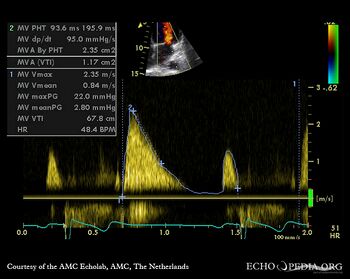

PSAX: Color Doppler, mild excentric aortic regurgitation Continuous-wave signal of transaortic flow: aortic bicuspid valve stenosis

PSAX: double orifice of mitral valve Continuous-wave signal of mitral inflow